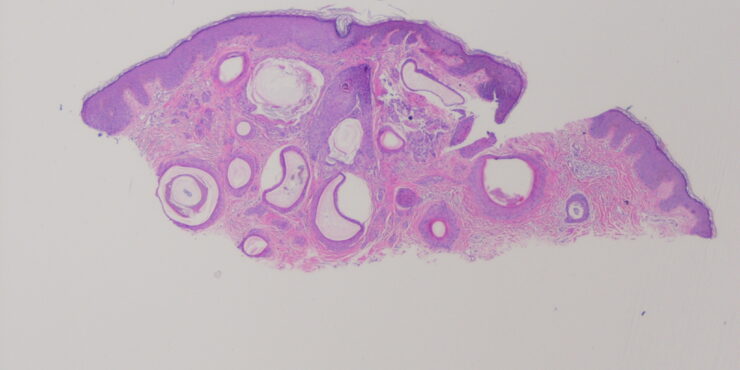

Read MoreTrichoepithelioma =ورم ظهاري شعري Trichoepithelioma Trichoepithelioma occurs either in multiple lesions or as a solitary lesion. The name trichoepithelioma is preferable to other designations, such as epithelioma adenoides cysticum and multiple benign cystic epithelioma, because it is more indicative that the differentiation of this tumor is toward hair structures. Multiple trichoepitheliomas are transmitted as an autosomal dominant trait (53). In most […]